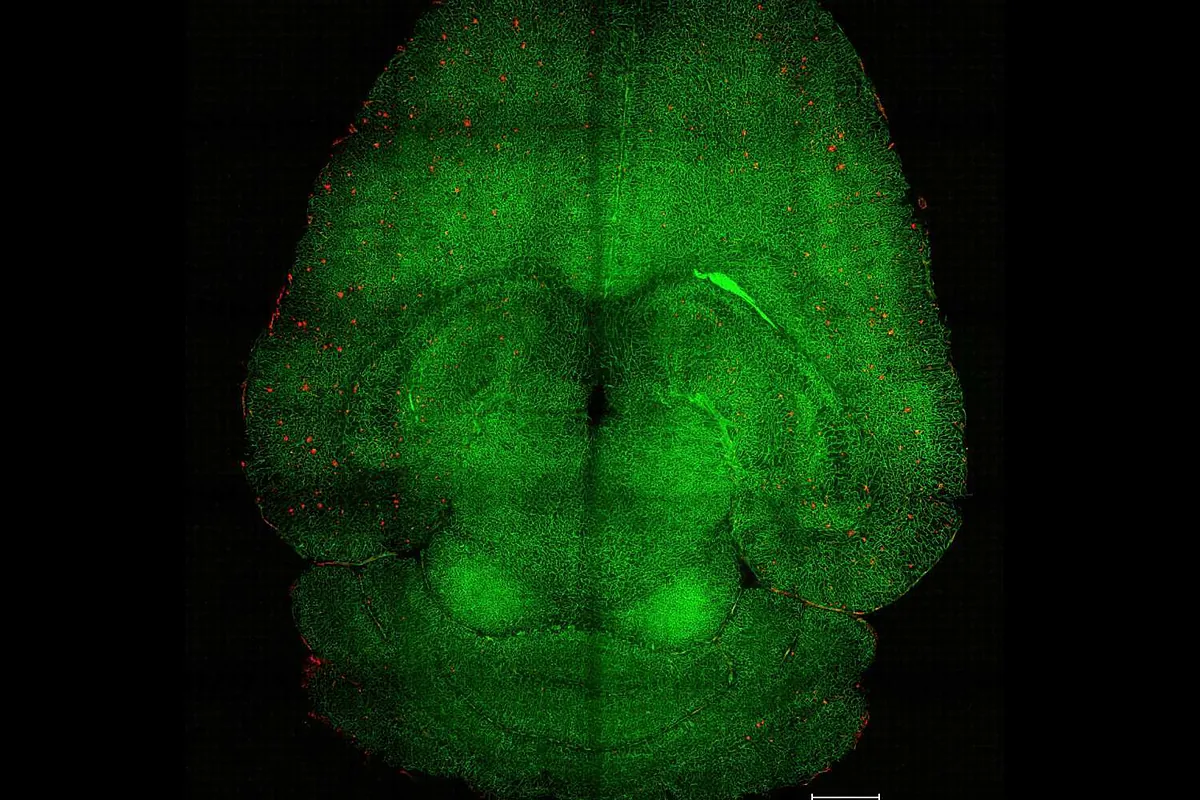

Científicos revierten el alzhéimer con nanopartículas a través del sistema vascular

Con solo tres inyecciones de estas moléculas, los animales experimentaron una recuperación de las capacidades cognitivas con un efecto que duró el equivalente a 20 años humanos...